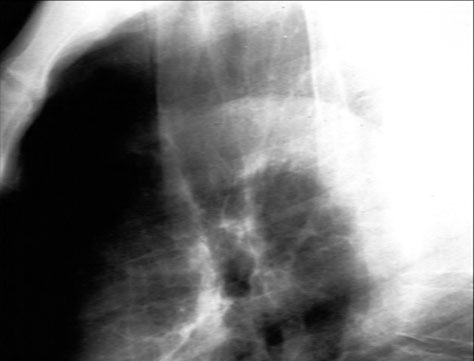

Note dark line representing air in front of trachea